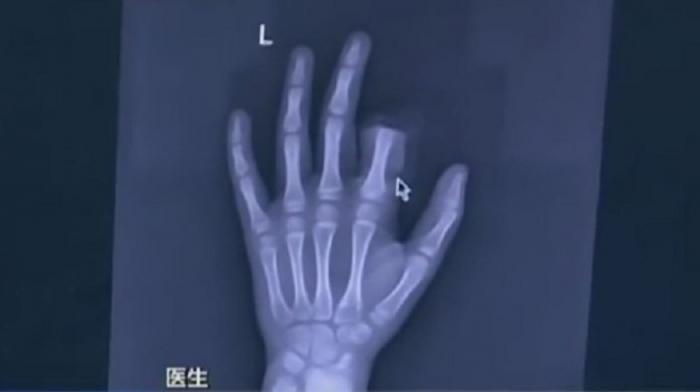

Atenție, părinți! Gestul șocant făcut de un copil după ce părinții i-au interzis accesul la smartphone

Micuții noștri petrec din ce în ce mai puțin timp în aer liber și prea mult în fața laptopului sau a telefonului mobil. Totuși, până unde poate merge această dependență?